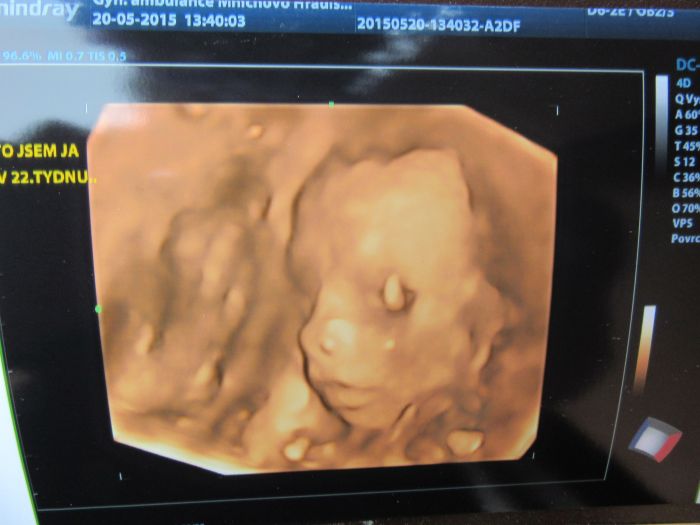

Ahojky, tak dneska jsme byli s manželem na 3D a máme potvrzenou malou fešandu. I přesto, že jsme si přáli kluka tak nakonec jsem spokojená, že to bude holčička. Doktor nám taky řekl, že je vše v pořádku a to je to hlavní. Přikládám fotečky, jsem z malý opravdu nadšená.